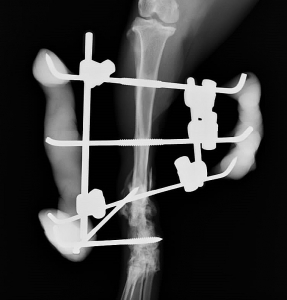

条件が整いましたので、上腕骨骨折、脛骨骨折を2回に分けて整復手術を実施いたしました。上腕骨骨折の説明と経緯は話題が散漫になりますので今回は割愛いたします。脛骨骨折の手術後が下の2枚の写真です。上写真が外観、下がそのレントゲン写真です。

写真をご覧になって、なんだか痛々しそうな、少々大げさな感じを受けた方は多いのではないかと思いますが、こういった骨折の整復手術の方法を「創外固定法」と呼びます。読んで字のごとく「傷の外で固定する方法」です。

この方法は骨に本来かかる様々な力を、骨を貫通する金属ピンを通じて周囲の金属ロッド(写真で棒のように見えるもの)や、レジン(写真で灰色の粘土のように見えるもの)で受けて内部の骨折を外で固定する骨折整復法のひとつです。

オレンジ矢印の部分で骨折端が体外に飛び出しており、廃液(膿などの液体が出ること)しておりましたので、そこにはドレーン(排泄のための管)を設置して、感染の治療を同時に行っていきます。

創外固定法には様々な利点と適用例があるのです。(字数を消費するのでこのコラムでは割愛させていただきますが。)今回この方法を選んだ大きな理由はこの骨折が複合骨折(粉砕骨折)であると同時に特にその一部が、開放骨折(複雑骨折)であったからです。ちょっと面倒な説明ですが、以下をお読みください。